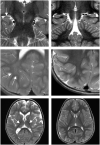

Early infantile epileptic encephalopathy-44 (EIEE44, MIM: 617132) is a previously described condition resulting from biallelic variants in UBA5, a gene involved in a ubiquitin-like post-translational modification system called UFMylation. Here we report five children from four families with biallelic pathogenic variants in UBA5 All five children presented with global developmental delay, epilepsy, axial hypotonia, appendicular hypertonia, and a movement disorder, including dystonia in four. Affected individuals in all four families have compound heterozygous pathogenic variants in UBA5 All have the recurrent mild c.1111G > A (p.Ala371Thr) variant in trans with a second UBA5 variant. One patient has the previously described c.562C > T (p. Arg188*) variant, two other unrelated patients have a novel missense variant, c.907T > C (p.Cys303Arg), and the two siblings have a novel missense variant, c.761T > C (p.Leu254Pro). Functional analyses demonstrate that both the p.Cys303Arg variant and the p.Leu254Pro variants result in a significant decrease in protein function. We also review the phenotypes and genotypes of all 15 previously reported families with biallelic UBA5 variants, of which two families have presented with distinct phenotypes, and we describe evidence for some limited genotype-phenotype correlation. The overlap of motor and developmental phenotypes noted in our cohort and literature review adds to the increasing understanding of genetic syndromes with movement disorders-epilepsy.